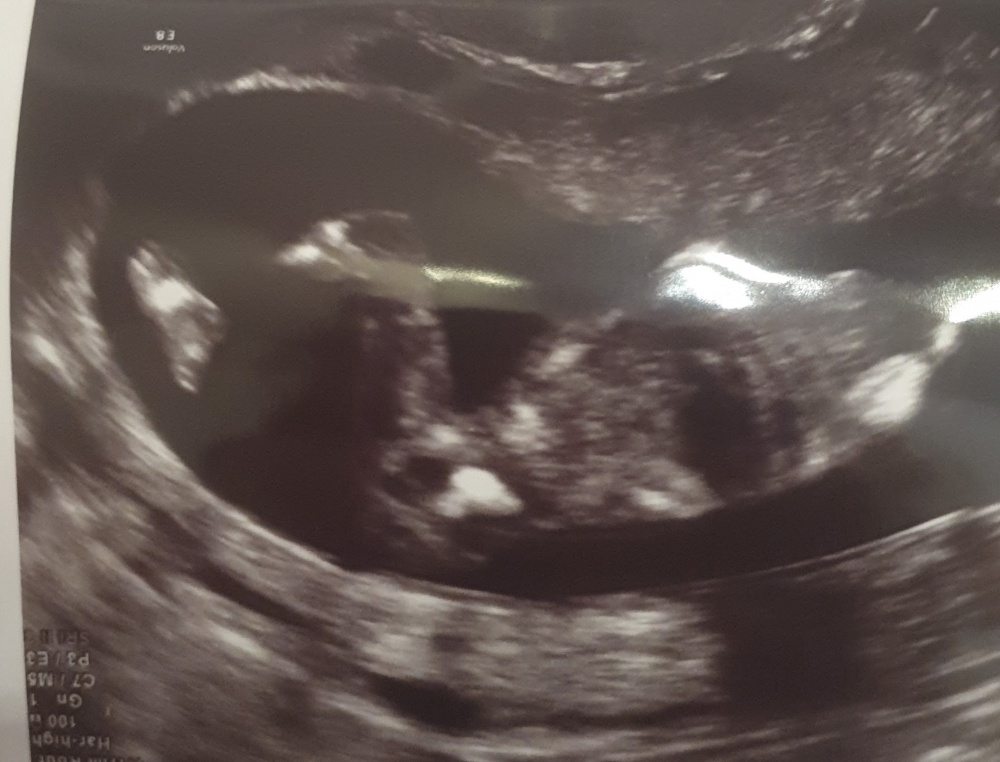

Hallo. Ich war diese Woche bei meiner Frauenärztin (17+1) und sie war sich beim Geschlecht sofort sicher

Was sagt ihr? Ist es wirkich ein Junge? <br>

Was sagt ihr? Ist es wirkich ein Junge?